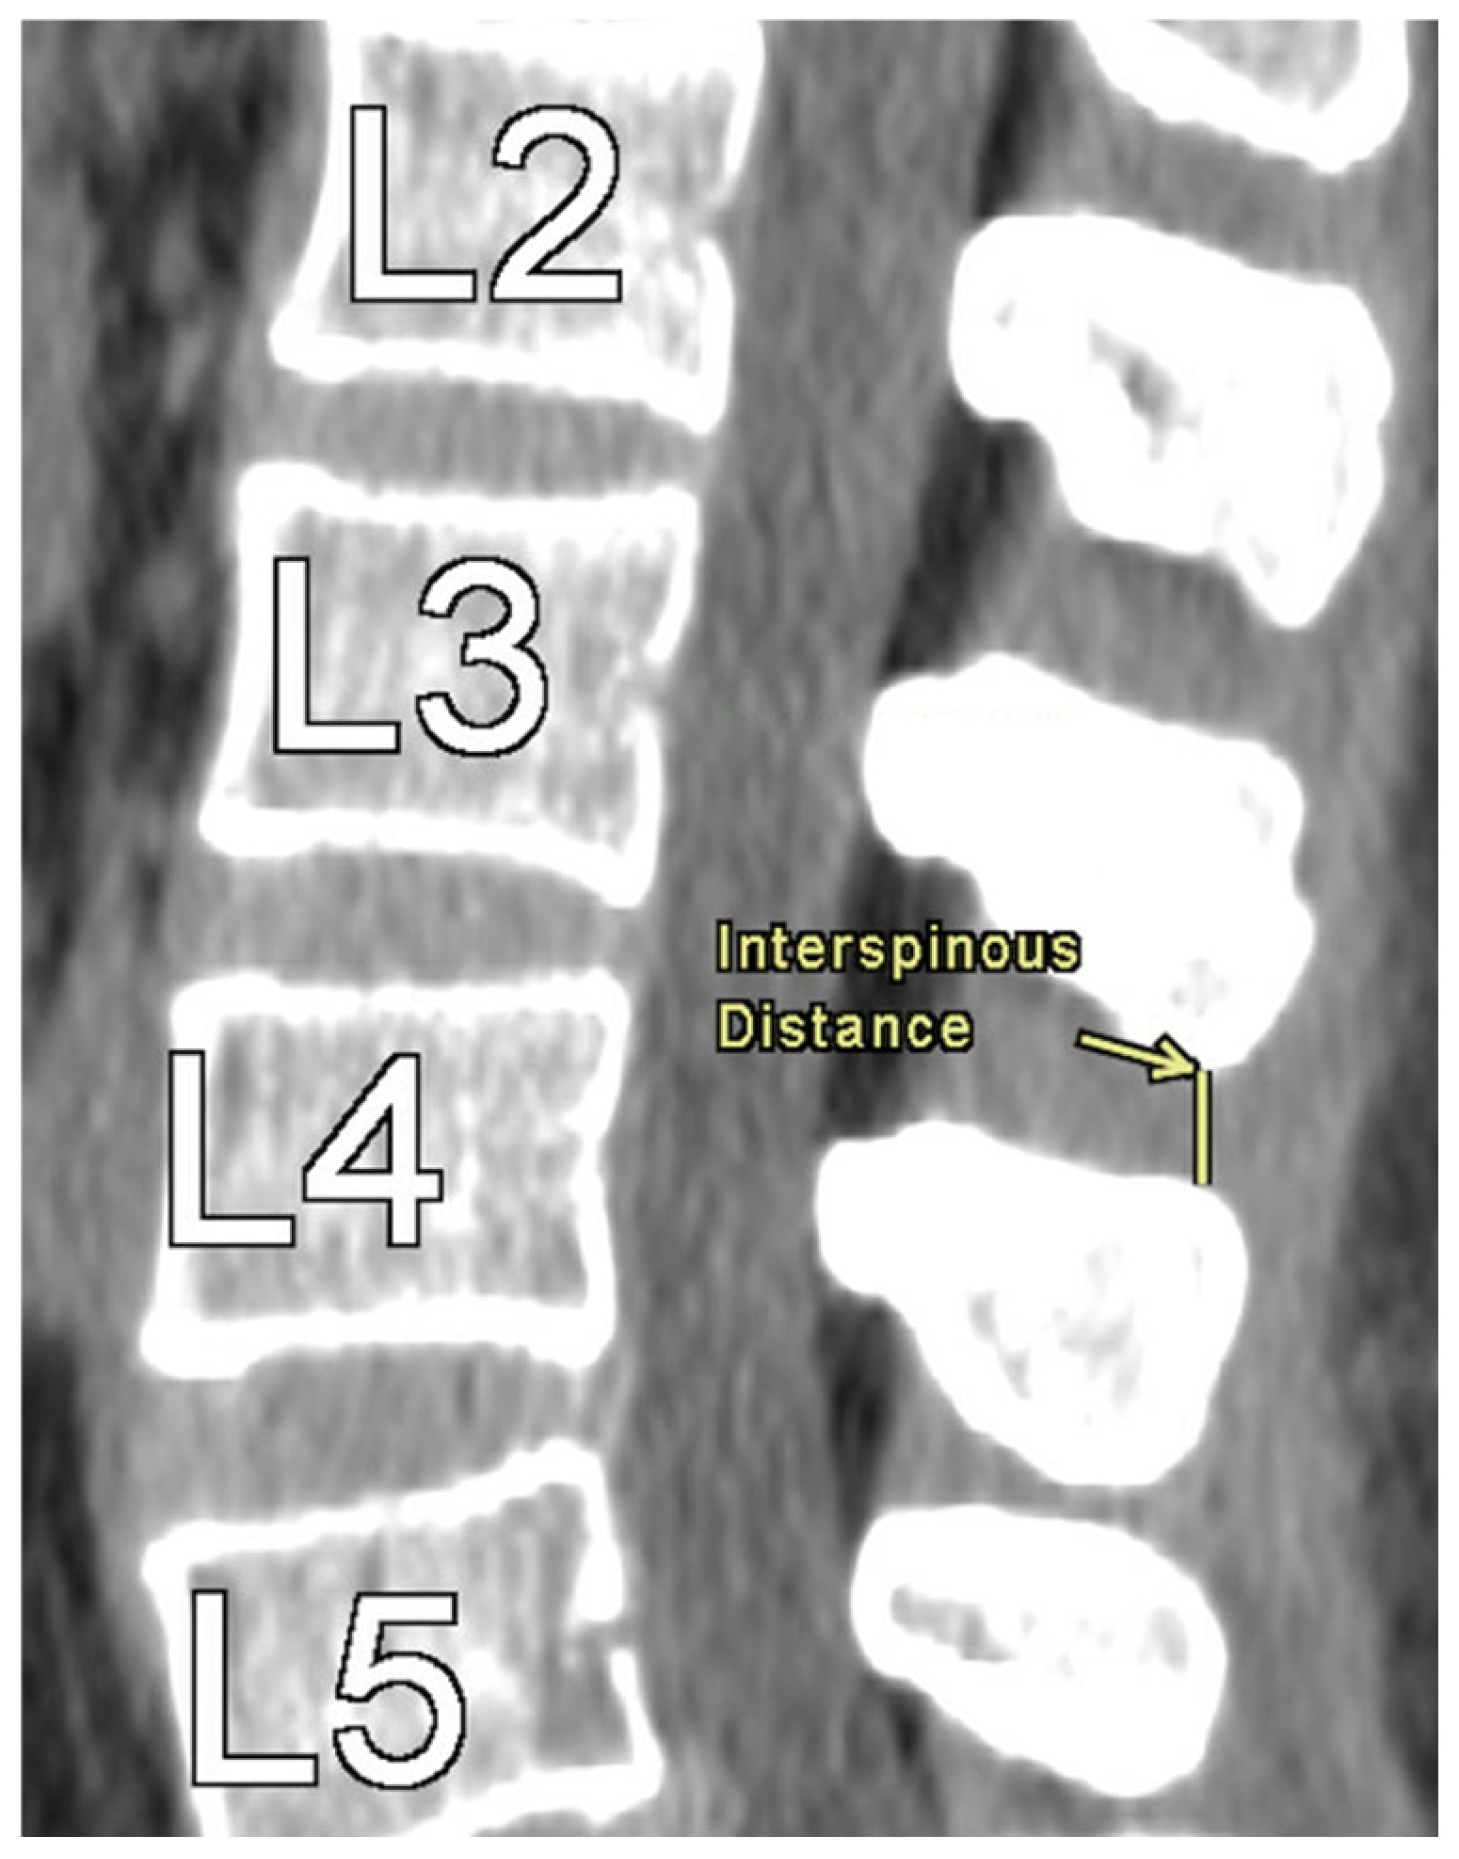

The authors took axial and sagittal CT imaging measurements and first located the midline of the lumbar spine in both views. Then, the measurements were taken at each level from L1 to L5. Figure 1 provides an illustration of the measurement technique for ISD, measured as the shortest vertically linear distance between the most caudal tip of the superior spinous process down to the top of the inferior spinous process in the mid-sagittal plane. DSH was measured between each vertebra using sagittal CT views and recorded in the mid-sagittal plane anteriorly, at the middle, and posteriorly. These distances were defined as the shortest vertical distances between the superior and inferior endplates at their respective vertebra, as illustrated in Figure 2.

Figure 1. Interspinous Distance Measurement at L3-L4.